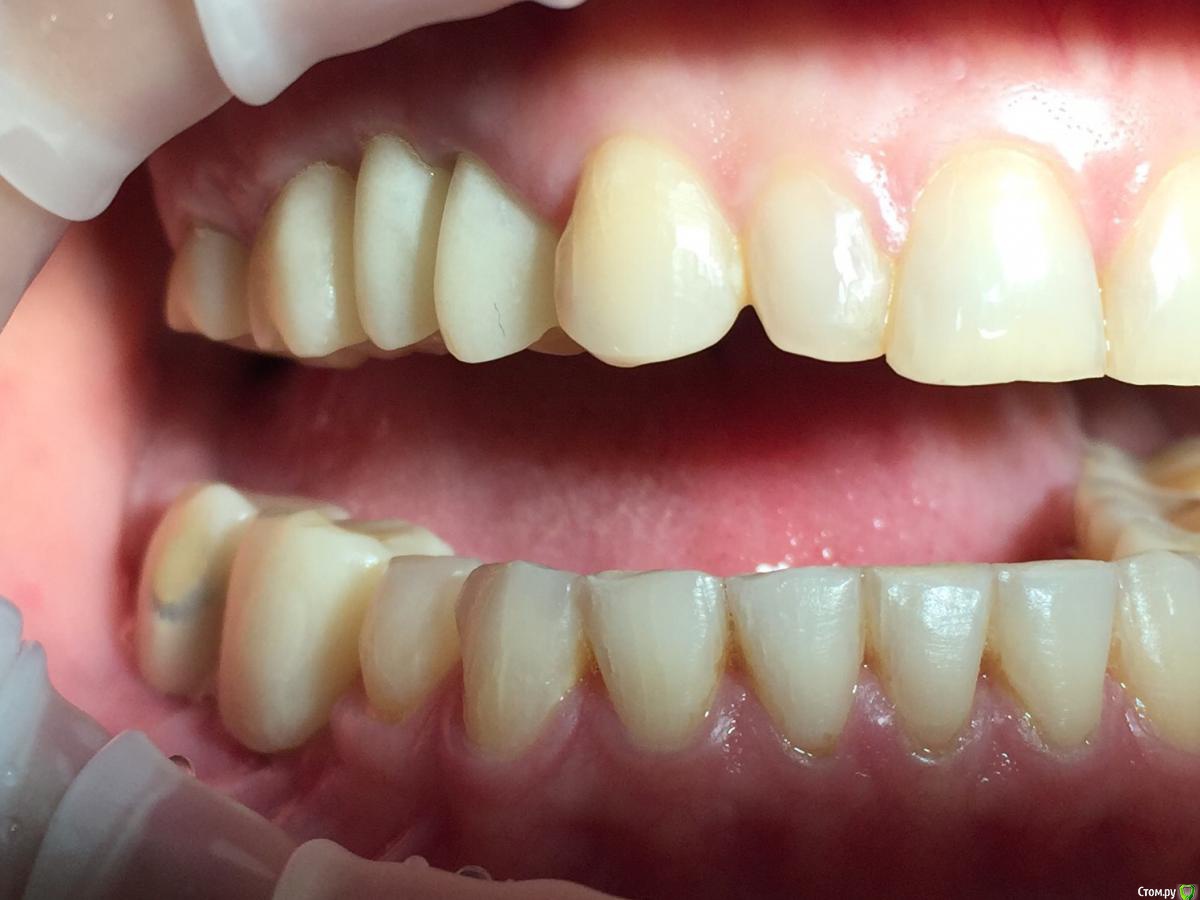

Глеб Митрофанов Опубликовано 12 сентября, 2015 Поделиться Опубликовано 12 сентября, 2015 (изменено) Направлена ортопедом , к которому пришла от другого хирурга и ортопеда , которые оперировали и изготавливали времянки соответственно . Пришла с просьбой - хочу сосочки ! Изменено 12 сентября, 2015 пользователем Глеб Митрофанов Ссылка на комментарий

Глеб Митрофанов Опубликовано 12 сентября, 2015 Автор Поделиться Опубликовано 12 сентября, 2015 А какой вопрос? С какой целью написали?Что возможно сделать , чтоб сделать максимально приближенное к желаемому ? Работа с мягкими тканями , времянками ?? Ссылка на комментарий

faity Опубликовано 12 сентября, 2015 Поделиться Опубликовано 12 сентября, 2015 пластика с бугров наверху, снизу полностью переделывать ортопедию и делать пластику с бугров. Гамборена вчера показывал как))) carlos показывает уже год 4 Ссылка на комментарий

Aquarius Опубликовано 12 сентября, 2015 Поделиться Опубликовано 12 сентября, 2015 Что возможно сделать , чтоб сделать максимально приближенное к желаемому ? Работа с мягкими тканями , времянками ??Если имплант не глушить, то по моему никак Ссылка на комментарий

Mane Опубликовано 12 сентября, 2015 Поделиться Опубликовано 12 сентября, 2015 снимаешь временную коронкупересаживаешь сст с бугра на тонкий формировательждешь месяцоцениваешьпротезируешь 2 Ссылка на комментарий